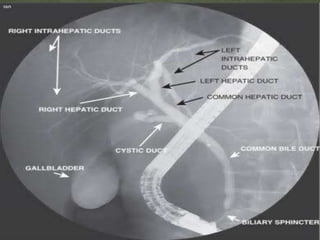

 MRCP is non invasive way to visualize hepatobiliary

tree.

 It can detect biliary and pancreatic duct stone

,strictures , and dilatations in billiary tree.

 Endoscopy plus fluoroscopy =ERCP

 It is an invasive procedure

 Has diagnostic and therapeutical potential

 Allows biopsy or brush cytology

 Allows stenting for stricture